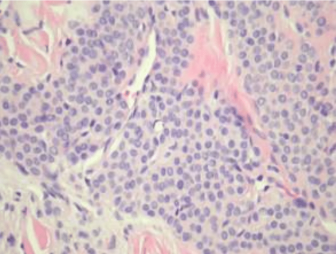

DERMATOHISTOPATHOLOGY:

Histopathologic studies revealed endothelium-lined spaces surrounded by monomorphous cells with pink and pale cytoplasm and round nuclei within the dermis.